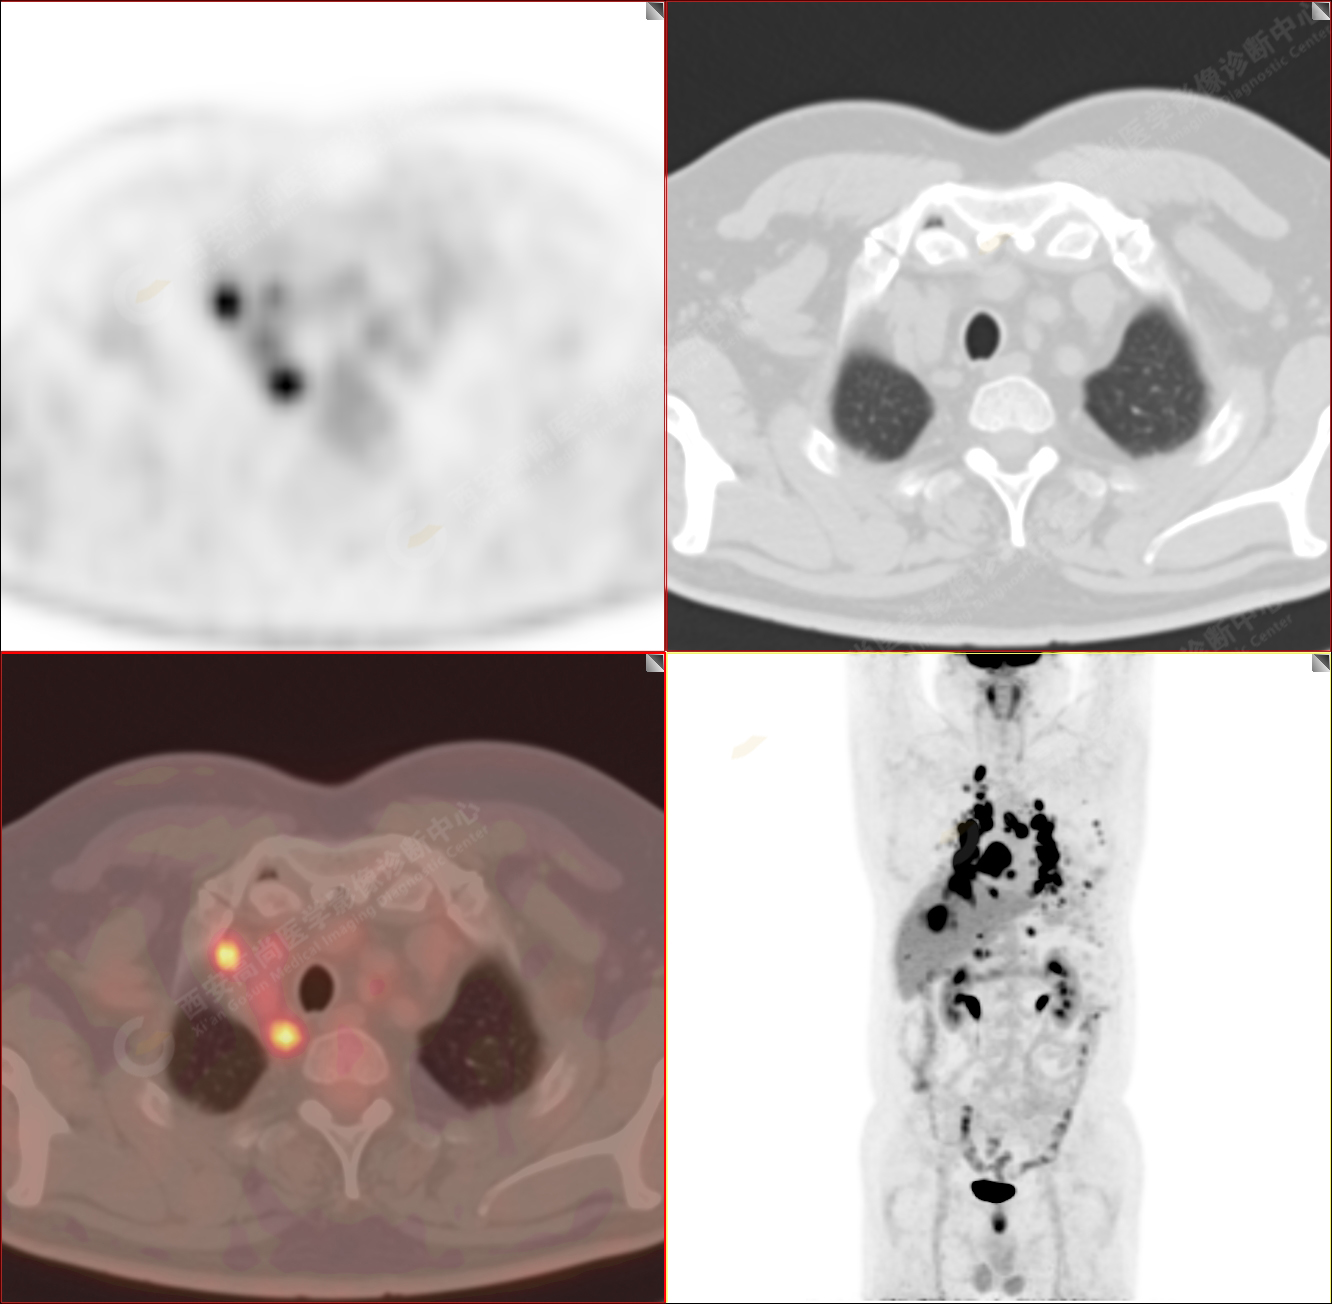

PET/CT-MR診斷結(jié)節(jié)病雙肺及全身多發(fā)淋巴結(jié)廣泛累及1例【西安高尚病例】

男性,53歲,頭暈半月入院,CT發(fā)現(xiàn)肺內(nèi)腫塊,雙肺多發(fā)大小不等實(shí)性及粟粒樣結(jié)節(jié),雙肺門(mén)及縱隔多發(fā)腫大淋巴結(jié)。病程中無(wú)發(fā)熱、胸悶氣及胸部不適。既往:左側(cè)肋骨外傷史。

PET/CT圖像